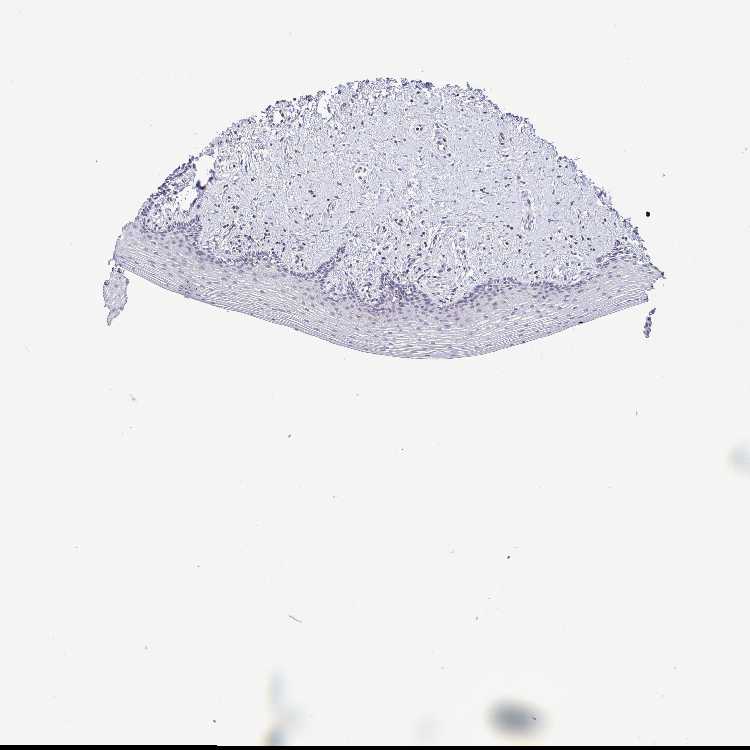

VAGINA - Antibody stainingi

Antibody staining in the annotated cell types in the current human tissue is reported as not detected, low, medium, or high, based on conventional immunohistochemistry profiling in selected tissues. This score is based on the combination of the staining intensity and fraction of stained cells.

Each image is clickable and will lead to virtual microscopy that enables deeper exploration of all samples and also displays staining intensity scores, fraction scores and subcellular localization as well as patient and tissue information for each sample.

Antibody HPA006480Antibody HPA025079

Squamous epithelial cells Not detectedNot detected